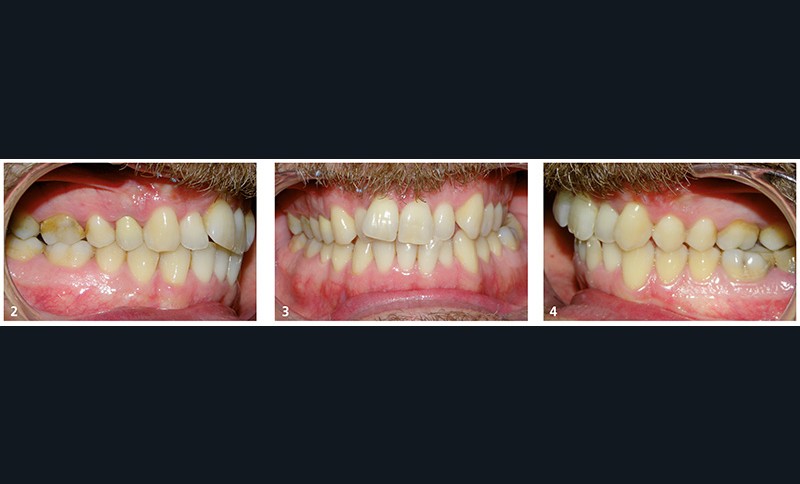

Il présente une malocclusion de classe II subdivison gauche totale par mésioposition du secteur 2 avec une déviation dentaire du milieu maxillaire à droite (fig. 2 à 6) dans un visage équilibré (fig. 7 et 8).

La mésioposition du secteur 2 a entraîné un encombrement antérieur avec malpositions des incisives supérieures, la 12 étant en occlusion traumatogène, en bout à bout avec son antagoniste (fig. 3). Dans le sens transversal, il existe une endoalvéolie maxillaire avec occlusion inversée postérieure à gauche. À l’arcade mandibulaire, l’encombrement est modéré (fig. 6).